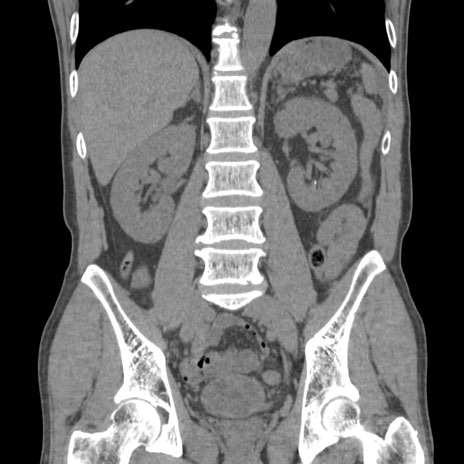

症例56 CT(冠状断像)

横断像